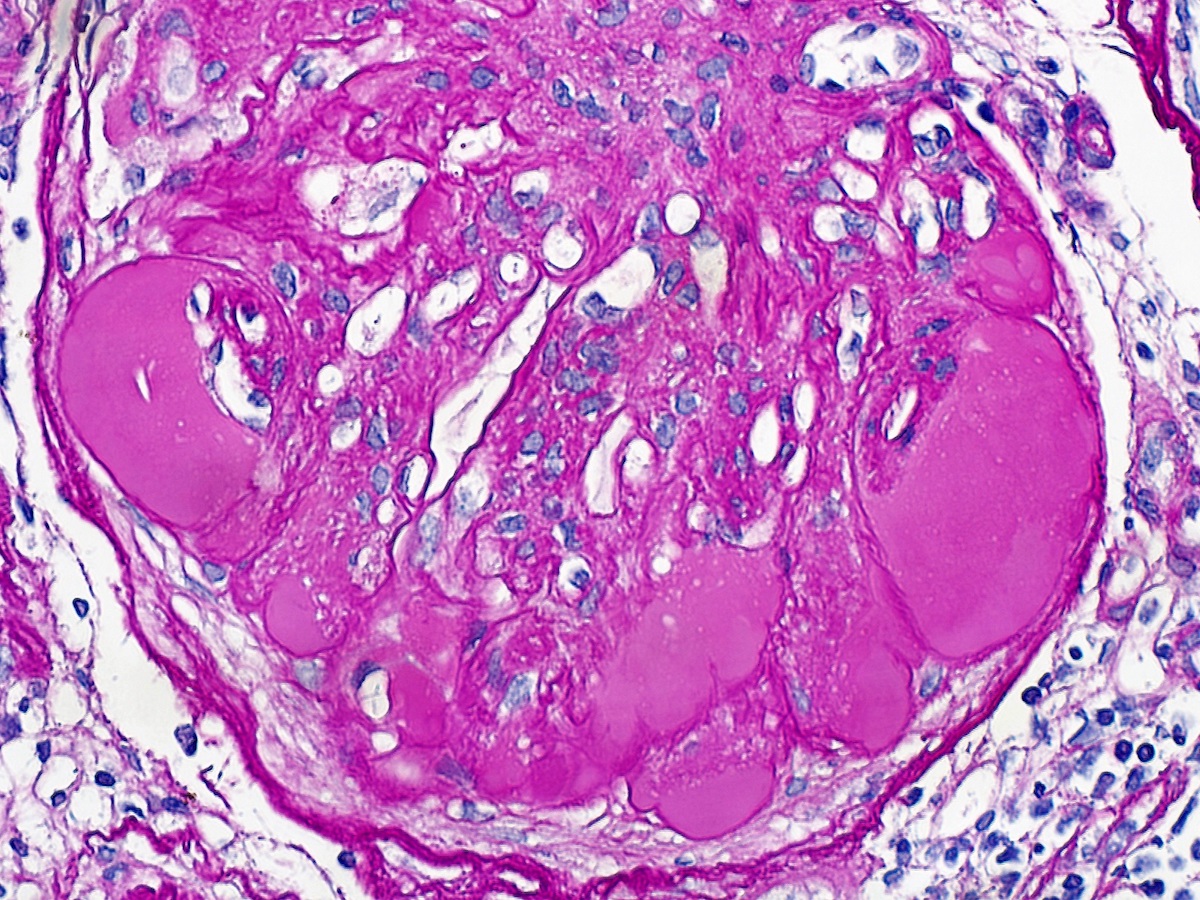

Microscopic (histologic) images

Contributed by Khaled A. Murshed, M.D., Noheir M. Taha, M.B.B.Ch., M.D. and Mohammed Akhtar, M.D.

Positive stains

- Expanded mesangium is positive for periodic acid-Schiff (PAS), Jones methenamine silver, trichrome

Microscopic (histologic) description

- Diffuse uniform thickening of glomerular basement membrane (GBM)

- Matrix expansion encroaching on the capillary lumina may be diffuse, nodular or both

- Nodular lesions are also called Kimmelsteil-Wilson lesions (Contrib Nephrol 2011;170:36)

- These later give rise to large solitary nodules, which may reveal a laminated architecture on Jones silver stain